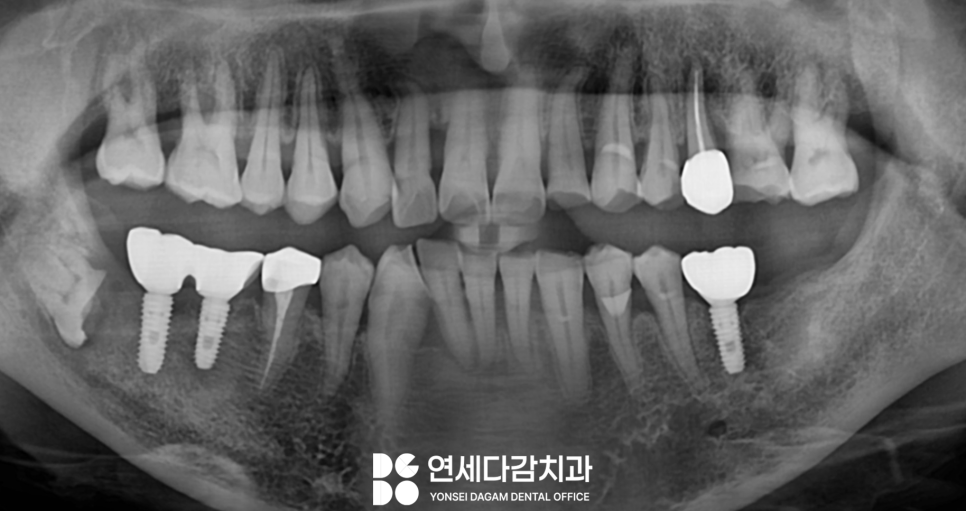

또 다른 케이스인데요.

이곳도 마찬가지로

오금역 치과 에서 앞서 보여드렸던

것과 같은 상황이었습니다.

이곳 또한 수평으로

매복되어 부분 맹출 된

상태로 잇몸 염증 및 통증을 일으키고 있었죠.

이 부위만 마취하에

잇몸을 절개하고 치아의

머리 부분인 치관만 조심스럽게 절단합니다.

치근만 남겨둔 상태로

봉합하여 치유되면

말끔한 잇몸으로 돌아오는데요.

세균이 들어올 공간이 사라지면서

뿌리는 안전하게 뼈 속에

묻어두게 됩니다.

물론 정기 검진을 통해

주기적으로 확인해 주는 것이 좋겠죠?